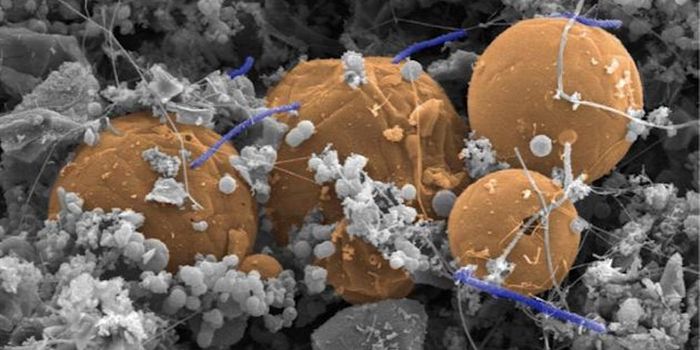

JAN 31, 2016MicrobiologyResearchers at the University of Notre Dame identified the mechanism by which Streptococcus pyogenes, also known as Grou ...